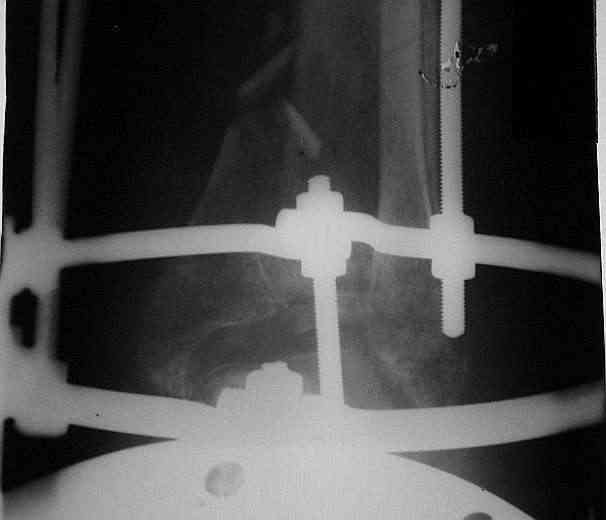

Здравствуйте, коллеги.Больной 26 лет, в 2004 году попал ко мне с диагнозом:синтезированный в аппарате Илизарова неполный внутрисуставной оскольчатый перелом дистального метафиза левой большеберцовой кости со смещением; выраженный остеопороз; множественное спицевое нагноение. Несостоятельность фиксации (костные отломки буквально "елозили" по спицам, несмотря наналичие упорных площадок).

Мной был демонтирован АВФ, удалены все спицы. Больной некоторое время лечился консервативно (шина Белера, антибиотики, перевязки). По заживлению и купировании гнойно-воспалительного процесса была произведена осткрытая репозиция, накостный остеосинтез 1/3 трубчатой пластиной.Такой вариант был принят из-за жуткого остеопороза и отказом больного от предложенного артродезирования голеностопного сустава сразу. Послеоперационный период без особенностей. Через год, больной пришел на осмотр на своих двоих, без дополнительной опоры, с жалобами на боли приходьбе в обл. г/стопа и с желанием замкнуть сустав. В операционной столкнулся с неожиданной проблемой по удалению пластины, она была глубоко вмурована в толщу склерозированного метафиза на глубину 1.5 см; удалить не рискнул (считал, что металл помешает в ходе реконструкции и требуется его удаление).

Было решено, уже по ходу операции, выполнить артродез болтом-стяжкой, тем самым компрессируя резецированные суставные поверхности и смещая стопу латерально, дабы нивелировать варусную деформацию и восстанавливая тем самым опорную ось всей конечности.

Вчера (прошло около 8 месяцев)больной обратился ко мне в очередной раз с жалобами на боли умеренно-жгучего характера в области выстояния концов болта-стяжки. На момент осмотра:укорочение левой нижней конечности на 1,5 см; гипотрофия медиальной группы мышц голени и четырехглавой мышцы бедра; передвигается без дополнительной опоры в ортопедической обуви на растояние до 5 км; работает приемщиком цветных металлов (приходится перетаскивать грузы). Нарентгенограмме, насколько это можно видеть, костного блока сформировать не удалось, но движений в голеностопном суставе нет - ни активных, ни пассивных. Послеоперационные рубцы б/о; свищей и нагноения не было. Активно больногонаблюдать не приходилось, т.к. проживает в другом городе.

ЗЫ: Прошу прощения за очень низкое качество представленных ренгенограмм. Буду очень признателен за комментарии.